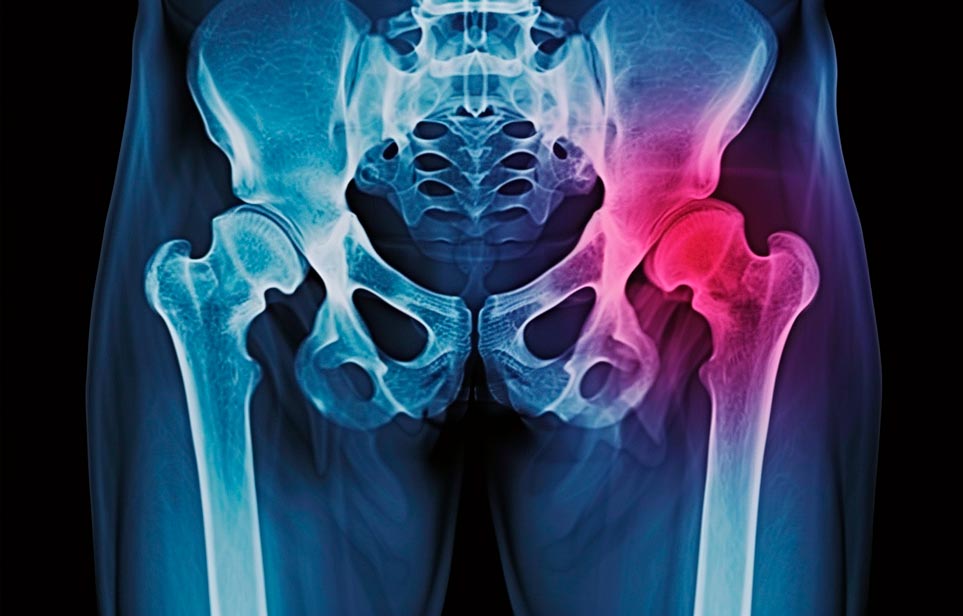

Реабилитация пожилых после перелома шейки бедра в Симферополе

Эффективная и профессиональная реабилитация после перелома шейки бедра в Симферополе осуществляется по демократичным ценам лучшими специалистами современной медицинской клиники «Заботливые люди» с применением персонального подхода к каждому пожилому человеку с такой тяжёлой травмой бедренной кости ноги. В процессе осуществления такой специализированной услуги все наши пациенты имеют возможность получения качественного и достойного обслуживания, эффективного восстановления. Лучший дом престарелых позаботиться о Вашем близком человеке.

Такая травма в большей части случаев возникает у граждан преклонного возраста. При её появлении на протяжении длительного времени сохраняются болевые и неприятные ощущения в области паха, при которых серьёзно ухудшается качество жизни, возникает множество последствий для его жизни и здоровья.

По какой симптоматике можно определить перелом шейки бедра?

Выявить его можно по возникновению следующей тревожной симптоматики:

- Визуально повреждённая нога сокращается на несколько сантиметром из-за сокращения мышц.

- Стопа выворачивается наружу.

- В лежачем положении человек не может поднять ногу.

При такой симптоматике важно незамедлительно обращаться к специалистам для получения всей необходимой помощи, терапии и восстановления после перелома шейки бедра. Если не оказать помощи старику, то это приведёт к гноению, инвалидности, иным видам осложнений.